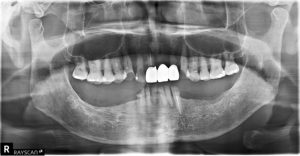

全口吸附式活動假牙案例分享1

全口吸附式活動假牙案例分享2

其他 BPS 活動假牙 案例分享